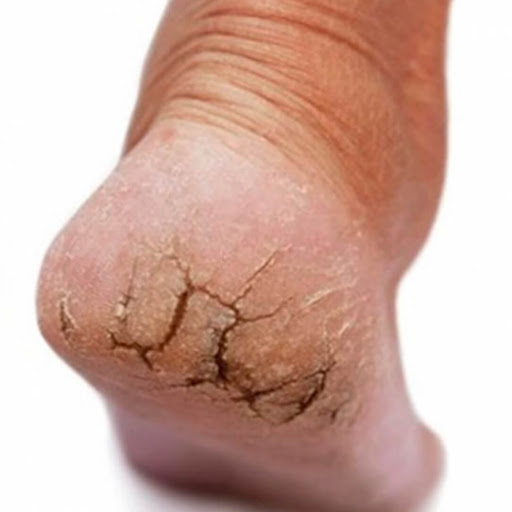

RACHADURA NOS PÉS

O que são Rachaduras nos Pés:

As rachaduras nos pés são fissuras ou fendas na pele, geralmente na região dos calcanhares, causadas por ressecamento, atrito ou pressão excessiva. Essas fissuras podem variar de pequenas rachaduras superficiais a fissuras mais profundas que podem causar dor e desconforto.

Sintomas:

Fissuras ou fendas na pele, geralmente nos calcanhares.

Pele seca e escamosa ao redor das rachaduras.

Sensação de dor ou desconforto ao caminhar ou ao ficar em pé.

Sangramento ou secreção de fluido das fissuras, especialmente se forem profundas.